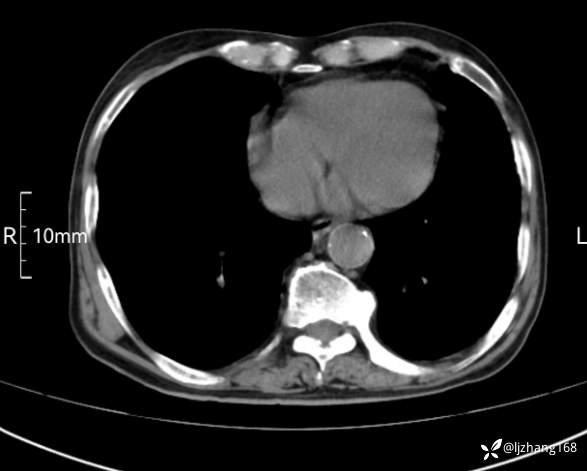

辅助检查:胸部CT:双肺肺气肿,间质性病变,血气分析:PH 7.413, PCO2 29.2mmHg, PO2,81.8mmHg,乳酸 3.3mmol/1,剩余碱-4.0mmol/1,HC03 18.8mmol/1。全血超敏C反应蛋白:超敏C反应蛋白 135.60 mg/L、 白细胞 14x19^9/L,中性粒细胞11.6x10^9/L。